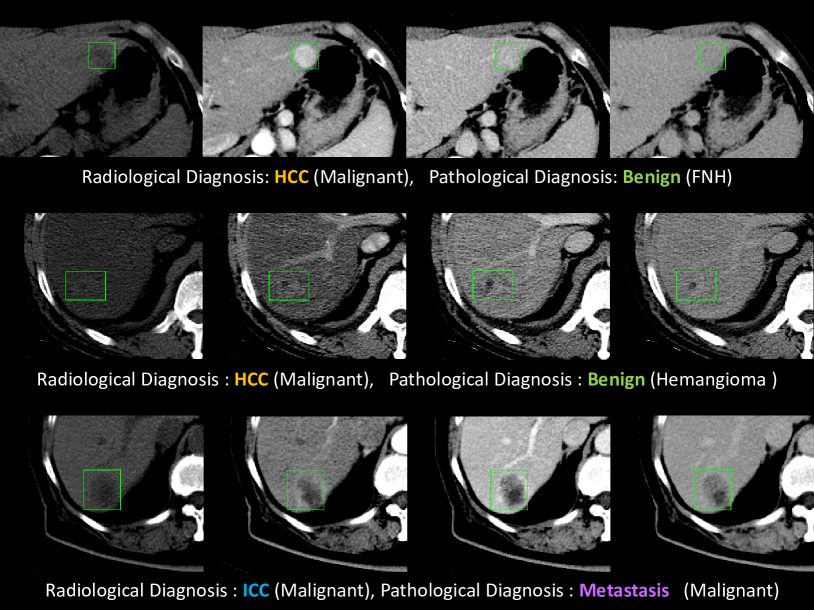

Why is this a difficult problem? Although clinical diagnoses from multi-phase \acpCT are usually performed through consensus between radiologists and clinicians, misdiagnoses remain (Fig. 1). For instance, benign and \acICC lesions can be misinterpreted as \acHCC [13, 14], with separating \acHCC from hemangioma being a particularly pernicious difficulty [15, 16] . Solitary liver metastases are also difficult to differentiate from \acICC [17] (Fig. 1). Underscoring this, a 2006 retrospective study [13] investigating patients receiving a liver transplant to treat radiology-confirmed \acHCC, discovered that of the treated tumors were in fact benign. Even with the same scoring systems, inter-reader variability between radiologist is still a problem for reproducible diagnosis [18]. Khalili et al. [19] report that F1 scores for physicians differentiating \acHCC lesions from others is only . We aim to leverage computer-aided approaches to reduce the uncertainties in diagnosis, with many of the above challenging cases. In this work, we aim to differentiate lesions into four subclasses (\acHCC vs. \acICC vs. metastasis vs. benign), where even many human reader studies [20, 19] only focus on binary classification (\acHCC vs. others).